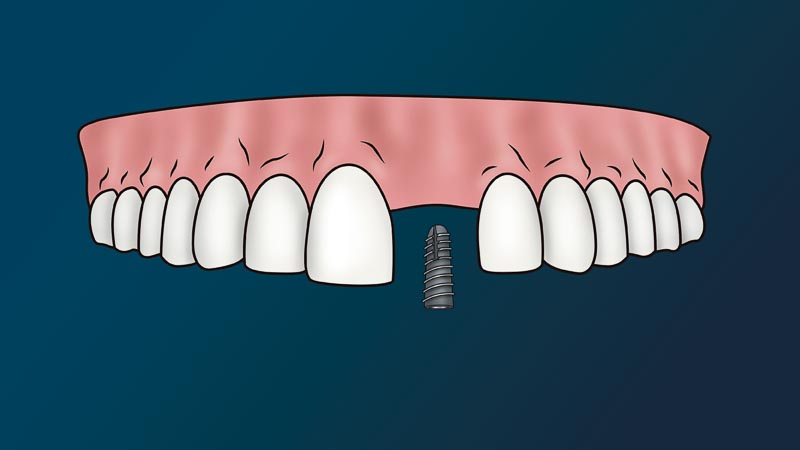

The dentist will attach to your jaw a metal root (implant) and place on top a fake tooth (crown). We call this procedure, a dental implant. Since this procedure is non-life threatening and non-essential to one’s immediate health, it considered a cosmetic procedure. In other words, medical or dental insurance policies don’t cover this procedure.

This procedure has an average cost of $3,000 -$7,000 per tooth in the United States. If a patient needs general anesthesia, bone grafting, or medications, there are additional costs. According to Forbes, full arch dental implant procedures in the United States can range from $30,000 – $90,000. This is crazy, and very different from the dental implant & all-on-4 cost in Mexico.

For the majority of us normal working Americans, the cost of dental implants can seem very intimidating. The mere thought of having to pay for something that can possibly cost up to $90,000 would cause most of us to lose sleep at night. However, as intimidating as it may sound, the fact is that when we have a problem that is affecting the quality of our lives and causing us pain, it can develop into very serious problems later on in life. At that point, we have no choice except to find a way to solve it. The longer a patient waits, the more serious the problem becomes.